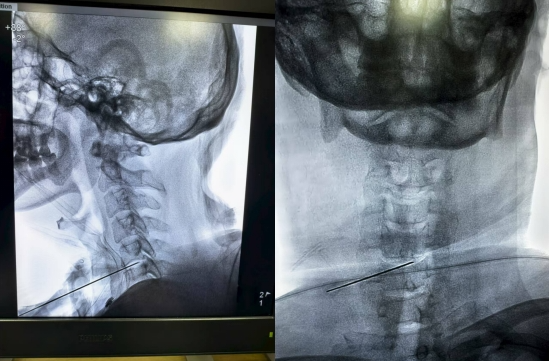

穿刺到位

来到我院疼痛科治疗,结合症状、体征及检查结果,汪庆玎主任医师带领团队讨论后,决定为他实施低温等离子射频消融术。术后,张先生的右上肢麻痛症状明显缓解,很快恢复了正常生活。

它的原理是通过一根细如针的穿刺针,精准到达病变的颈椎间盘位置,利用低温等离子体的能量,精准消融突出的髓核组织,减轻对神经根的压迫,从根源上缓解疼痛、麻木等症状。